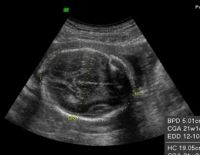

Tổng quan về kỹ thuật siêu âm 4D và những vấn đề liên quan

Siêu âm 4D là phương pháp chẩn đoán hình ảnh hiện đại, phổ biến trong lĩnh vực y học hiện nay. Kỹ thuật giúp quan sát trực tiếp các hoạt động của thai nhi, đồng thời hỗ trợ phát hiện những dị tật sớm ở...